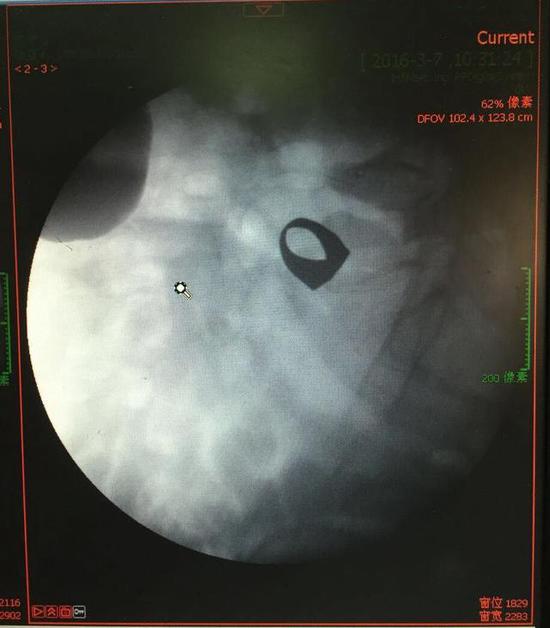

考慮到患者年齡較大,有冠心病,曾經(jīng)中過(guò)風(fēng),高血壓極高危級(jí),遂把老人安排在帶有監(jiān)護(hù)的病房,立即給予吸氧,補(bǔ)液等治療。醫(yī)院立刻開(kāi)啟綠色通道,醫(yī)護(hù)人員專(zhuān)門(mén)陪伴病人做了增強(qiáng)CT,腹部平片,和碘水造影,確定戒指的位置。檢查結(jié)果提示戒指位于右下腹小腸內(nèi),距回盲瓣體表投影約5cm。

在該院胃腸外科,舒曉剛教授、夏澤鋒副教授接診了張大爺,并制定下一步治療方案?紤]到患者年齡大,身體狀況不好,內(nèi)科基礎(chǔ)病較多,手術(shù)取戒指風(fēng)險(xiǎn)太大,花費(fèi)高。在綜合考慮后,胃腸外科專(zhuān)家組打算用微創(chuàng)結(jié)腸鏡技術(shù)嘗試取出戒指。結(jié)腸鏡一般用于結(jié)直腸檢查,一般很難通過(guò)回盲瓣,檢查到小腸,必須要有經(jīng)驗(yàn)的醫(yī)生來(lái)做。

3月9日,夏澤鋒教授細(xì)心的給病人做結(jié)腸鏡檢查,找到回盲瓣,調(diào)整結(jié)腸鏡鏡頭,快速的進(jìn)入小腸。結(jié)腸鏡緩緩上行至距離回盲瓣5cm的小腸,沒(méi)有戒指。繼續(xù)上行,至20cm的地方,仍然沒(méi)有找到戒指。

此時(shí)一個(gè)又一個(gè)大大的疑問(wèn)出現(xiàn)在每個(gè)在場(chǎng)的醫(yī)護(hù)人員腦海中,戒指還在小腸里嗎?戒指在哪個(gè)位置呢?夏教授立刻聯(lián)系放射科,拍片子,發(fā)現(xiàn)戒指已經(jīng)移動(dòng)了,從右側(cè)移動(dòng)到了左側(cè)去了。放射科醫(yī)師建議,戒指有可能會(huì)繼續(xù)沿腸道下行,如果過(guò)了回盲瓣,就可以自行排出,免除手術(shù)痛苦。教授們采納了這個(gè)意見(jiàn),立即給予促進(jìn)胃腸道動(dòng)力藥,枸櫞酸莫沙必利片,每日口服三次,另外配合灌腸治療,促進(jìn)腸道蠕動(dòng),利于戒指排出。